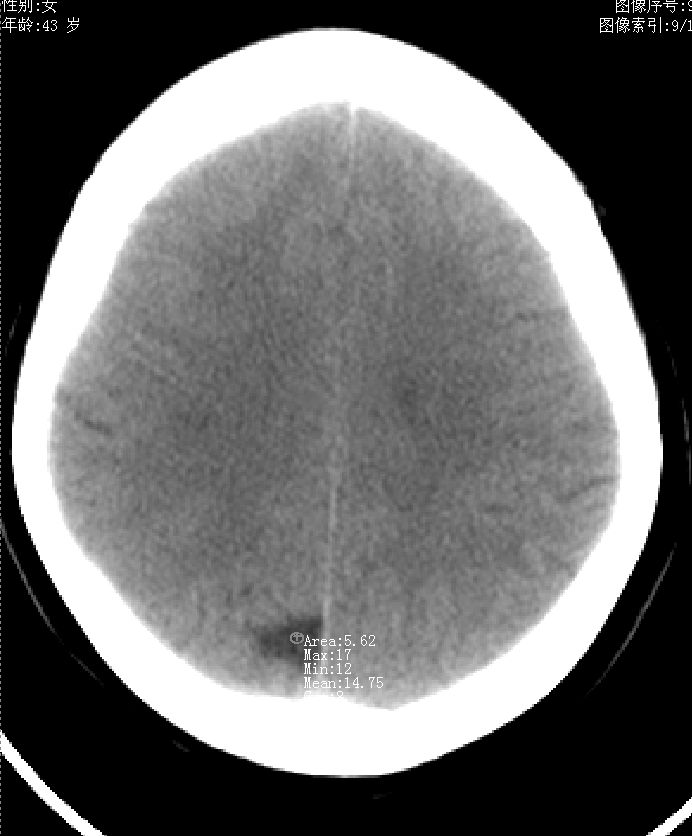

43岁,女性,头晕、语言含糊1天伴左侧肢体麻木,有高血压病史,bp160/100hg,余(-)。

右顶上小叶脑沟

脑沟或软化灶

脑沟或软化灶,建议增强或mr,最好mr

考虑右侧顶叶脑软化灶。

考虑右侧半卵圆中心陈旧性梗塞.

提示顶区局部脑沟!